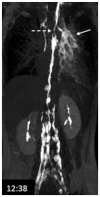

Background: Clinical examination and lymphoscintigraphy are the current standard for investigating lymphatic function. Magnetic resonance imaging (MRI) facilitates three-dimensional (3D), nonionizing imaging of the lymphatic vasculature, including functional assessments of lymphatic flow, and may improve diagnosis and treatment planning in disease states such as lymphedema.

Results: From 612 identified articles, 43 articles were included and their protocols and results summarized. Field strength was 1.5 or 3.0 T in all studies, with 25/43 (58%) employing 3.0 T imaging. Most commonly, imaging of the peripheries, upper and lower limbs including the pelvis (32/43, 74%), and the trunk (10/43, 23%) is performed, including two studies covering both regions. Imaging protocols were heterogenous; however, T2 -weighted and contrast-enhanced T1 -weighted images are routinely acquired and demonstrate the lymphatic vasculature. Edema, vessel, quantity and morphology, and contrast uptake characteristics are commonly reported indicators of lymphatic dysfunction.